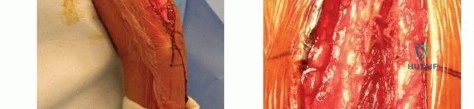

The Anterolateral Approach

The skin incision is made along a line connecting the coracoid process to the lateral epicondyle of the humerus. The length of the incision is dictated by the fracture pattern and the templated plate length. Subcutaneous tissues are dissected, taking care to identify and protect the cephalic vein, which can be retracted either medially or laterally depending on the exact proximal extent of the exposure.

The deep fascia is incised in line with the skin incision. The biceps brachii muscle is identified and mobilized medially, exposing the underlying brachialis muscle. At this juncture, the surgeon must decide on the specific handling of the brachialis muscle based on the fracture location.

For midshaft fractures, the brachialis muscle is split longitudinally down its midline. Because the medial half is innervated by the musculocutaneous nerve and the lateral half by the radial nerve, this longitudinal split is an internervous plane that preserves the function of both segments. The split is carried down to the periosteum, and the muscle halves are elevated off the anterior humerus. The lateral half of the brachialis acts as a protective muscular cushion between the retractor (and subsequently the plate) and the radial nerve.

For distal third fractures, the exposure must transition to the interval between the brachialis and the brachioradialis. The radial nerve emerges from the posterior compartment by piercing the lateral intermuscular septum and travels distally in the cleft between the brachialis (medially) and the brachioradialis (laterally).

To safely exploit this interval, the fascia between the brachialis and brachioradialis is carefully incised. The radial nerve must be actively identified and protected. It is often easiest to identify the nerve distally where the interval is wider and trace it proximally to where it pierces the septum. Once identified, the nerve is gently mobilized and protected with vessel loops. Retraction of the nerve must be minimal and meticulous to prevent iatrogenic neuropraxia.